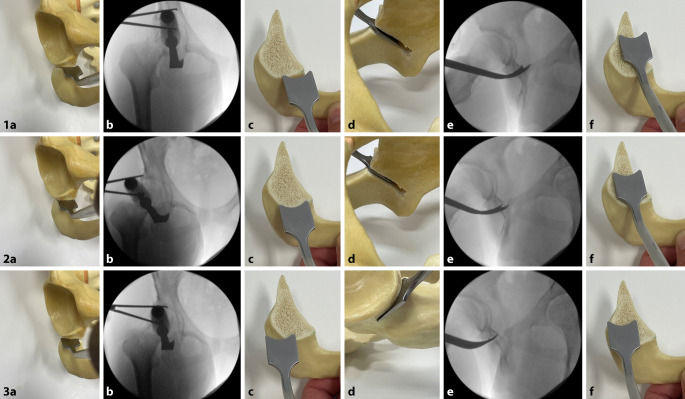

Spezielle gerade und gebogene Osteotome (nach Ganz, nach Lambotte; Abb. 2)

(Abb. 3, 4, 5, 6, 7, 8, 9, 10, 11, 12, 13, 14, 15, 16 und 17).

Die Schambeinosteotomie sollte mit einer kleinen oszillierenden Säge begonnen und mit einem geraden Osteotom abgeschlossen werden, um eine unkontrollierte Spaltung des Schambeins zu vermeiden. Die Schambeinosteotomie sollte ebenfalls nach kaudal und medial gerichtet sein. Eine zu vertikale Ausrichtung der Schambeinosteotomie kann zu einer Lateralisierung des Pfannenfragments führen, wodurch evtl. eine Medialisierung des Schambeins eingeschränkt sein kann.

Die supraazetabuläre Osteotomie sollte mindestens 3 cm kranial der Hüftgelenkpfanne durchgeführt werden, um genügend Raum für die Insertion der 2 Schanz-Schauben zu schaffen und eine stabile Schraubenfixation zu ermöglichen.

Die retroazetabuläre Osteotomie sollte in der Mitte der hinteren Pfannensäule liegen und nicht zu nahe an der Hüftpfanne durchgeführt werden. Der Knochen direkt hinter der Hüftpfanne ist sehr dick und schwierig komplett zu osteotomieren. Wenn die retroazetabuläre Osteotomie nicht vollständig durchgeführt wird und bei der Reorientierung des Azetabulumfragments zu viel Kraft über den Laminaspreizer aufgebracht wird, besteht die Gefahr, eine intraazetabuläre Fraktur durch die Fossa acetabuli zu induzieren.

Gefahr von intraazetabulären Frakturen: Die intraoperative Durchleuchtung ist obligat, um Komplikationen bei der Durchführung einer PAO zu vermeiden. Insbesondere hat sich die Durchleuchtung als zuverlässiges diagnostisches Werkzeug zur Vermeidung von Verletzungen der hinteren Säule und intraartikulärer Osteotomien erwiesen.